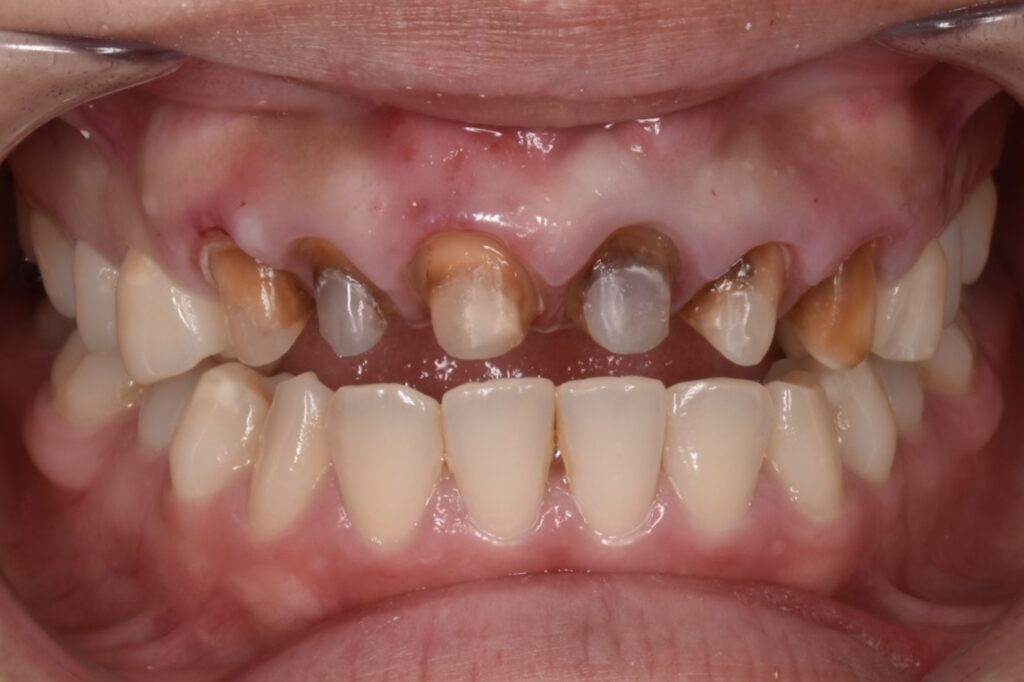

20代女性 20代前半の頃大阪にある有名審美歯科で前歯6本のセラミック矯正治療を受けた。強い痛みはないが、歯茎は赤黒く腫れていて真ん中で割れて、すでに連結してあるセラミックが脱落している状態です。とご相談くださいました。

初診時の状態

白い6連結のセラミックがありますが、右側のセラミックの前歯は破折しています。(写真左)また6連結の中央でジルコニアのフレームごと破折していることも確認できます。(写真中央)左の前歯は神経処置がされておらず穴だけ開いた状態でした。(神経治療途中?)土台6本全てが茶色から黒色に変色している事が周囲の天然歯と比べてもわかります。